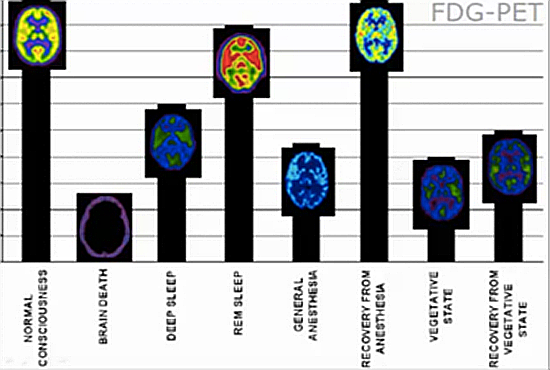

脑部疾病

脑功能代谢方面虽然目前我们医院开展不多,但是在癫痫灶定位、早老性痴呆的诊断等方面已经显示出他的特殊价值,未来还有很多可以探索的地方。

-脑也是葡萄糖代谢旺盛的器官,18F-FDG PET/CT全脑呈现高代谢状态,同理脑部肿瘤探测的灵敏度也较差,因而目前专门用其来探测脑部肿瘤的情况很少。